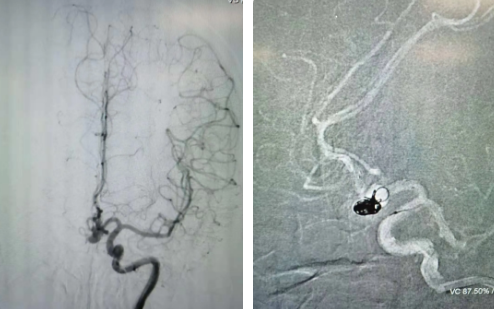

近日,西安國(guó)際醫(yī)學(xué)中心醫(yī)院腦科醫(yī)院為患者實(shí)施行Atlas支架輔助顱內(nèi)動(dòng)脈瘤栓塞術(shù),成功拆除了患者腦部的“不定時(shí)炸彈”。

經(jīng)過(guò)全面仔細(xì)評(píng)估,西安國(guó)際醫(yī)學(xué)中心醫(yī)院神經(jīng)外科陸丹醫(yī)生決定采用微創(chuàng)介入進(jìn)行治療。在取得患者及家屬同意后,3月11日,陸丹醫(yī)生為患者行Atlas支架輔助顱內(nèi)動(dòng)脈瘤栓塞術(shù)。

腦血管較外周血管更為脆弱、迂曲,對(duì)術(shù)者的操作技術(shù)及精準(zhǔn)性要求特別高。術(shù)中,陸丹醫(yī)生通過(guò)股動(dòng)脈穿刺、置入微導(dǎo)管,再通過(guò)微導(dǎo)管將彈簧圏送入動(dòng)脈瘤腔內(nèi),利用彈簧圈的機(jī)械閉塞作用,達(dá)到防止動(dòng)脈瘤破裂的目的。術(shù)后,患者各項(xiàng)生命體征平穩(wěn)。

陸丹醫(yī)生介紹,此次腦科醫(yī)院首次采用Atlas支架輔助進(jìn)行顱內(nèi)動(dòng)脈瘤栓塞術(shù)。以往動(dòng)脈瘤栓塞術(shù)中的支架輸送導(dǎo)管較粗,支架順應(yīng)性差,易使載瘤動(dòng)脈移位,而Atlas支架的輸送導(dǎo)管很細(xì),輸送順滑,同時(shí)順應(yīng)性及貼壁性強(qiáng),能夠適應(yīng)迂曲的腦遠(yuǎn)端血管。